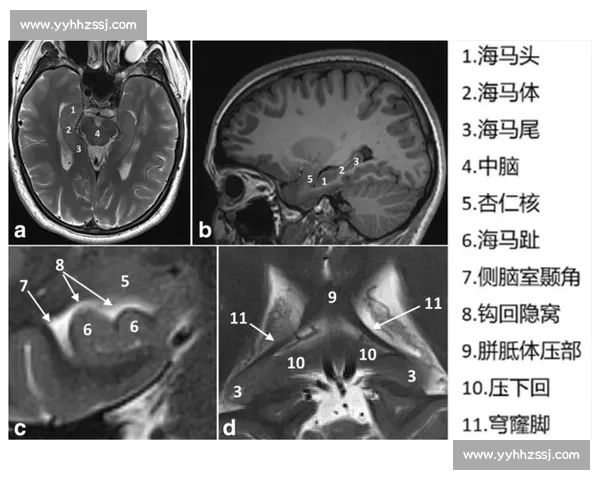

海马体位于大脑颞叶内侧,是边缘系统的重要组成部分,与杏仁核、扣带回等结构共同参与情绪、学习与记忆等高级脑功能。其内部结构主要包括齿状回、CA1、CA2、CA3区及下托区,不同亚区间通过复杂的神经纤维通路形成信息传递与整合网络。这种分层结构为海马体执行记忆编码和空间定位提供了形态学基础。